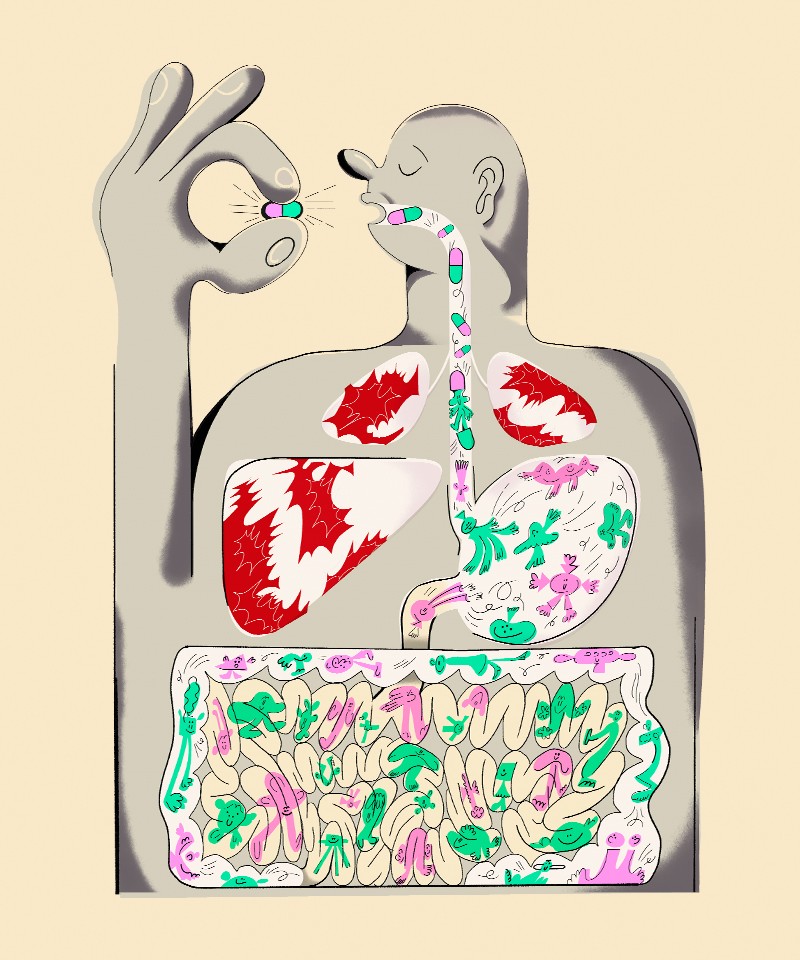

图:γ疱疹病毒感染后第8天,用H&E染色的CCR2-/-小鼠(Ly6Chi单核细胞缺乏)肺切片的组织学分析。

比利时Liège大学传染病系的研究人员进行的一项研究刚刚强调了Ly6C的重要作用嗨某些传染病中调节免疫反应的单核细胞。这项研究为与呼吸道病毒感染相关的各种严重免疫病理的治疗管理开辟了新的视角。

“然而,我们已经观察到在某些与gammaherpesvirus 如果感染,这种平衡被打破,就会导致严重的免疫病理。教授解释道。同样,在高致病性呼吸道病毒感染期间,这种保护性反应和有害反应之间的平衡被打破。为了更好地理解是什么决定了这种平衡状态,我们决定研究在被小鼠γ疱疹病毒MuHV-4感染期间调节气道炎症的免疫机制。特别地,我们剖析了单核细胞作为调节免疫反应的关键角色的作用。”

这项工作使ULiège的研究人员能够证明MuHV-4引起的肺部感染导致呼吸道中Ly6C的招募嗨能够调节宿主免疫反应的单核细胞。确实,Ly6C的缺失嗨单核细胞与严重的病毒诱导的免疫病理和促炎介质的全身释放有关。”

在机制上,病毒印迹单核细胞将CD4 T细胞招募到气道,其中一些是调节性T细胞。同时,这些单核细胞通过pD-L1/pD-1轴启动免疫抑制信号通路,减弱细胞毒性CD4 T细胞的有害激活。”席琳Maquet解释道。这些结果突出了Ly6C的作用嗨单核细胞在调节CD4 T细胞功能和识别分子途径作为潜在的治疗靶点,以减少与呼吸道病毒感染相关的严重免疫病理。事实上,具有细胞毒性功能的CD4 T细胞越来越受到人们的关注。它们存在于某些病毒感染,包括原发性EBV感染、抗肿瘤反应或自身免疫性疾病,已与疾病加重或保护性免疫诱导相关。关于细胞毒性CD4 T细胞对有益或致病性免疫反应的矛盾贡献,了解这些所谓的单核细胞“超级杀手”细胞的调节途径是非常重要的。

总之,γ疱疹病毒印迹单核细胞协调了细胞毒性和CD4 T细胞调节特性之间的平衡。总的来说,这项工作已经解剖了MuHV-4感染后肺部单核细胞和CD4 T细胞之间的复杂相互作用。”这项研究揭示了IL-10和pD-L1/pD-1信号通路在减少有害炎症方面的重要性,从而保护机体免受严重呼吸系统损伤和系统性疾病的发展。这项研究可能在γ疱疹病毒感染的背景之外,在各种病毒免疫病理的治疗管理中打开新的视角。